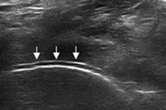

“双轨征”

跖趾关节软骨表面可见高回声不规则增强的软骨滑膜边缘线,呈“双轨征”。

高回声带

软骨表面回声增强,与深面的骨性关节面强回声线形成“双轨征”。

髁软骨的双轨征状,显示髌腱内部的聚集体